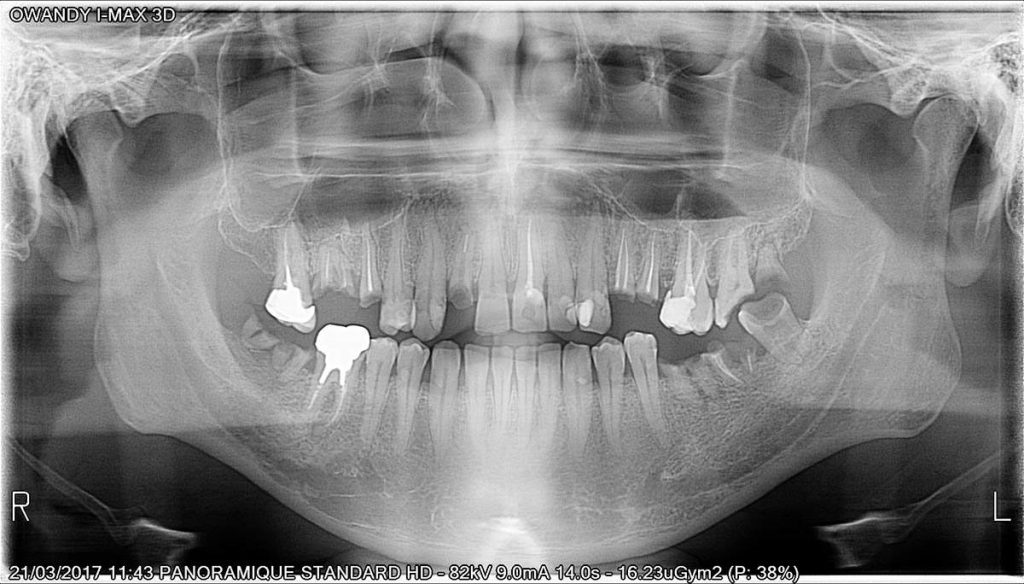

Calidad de imagen excepcional